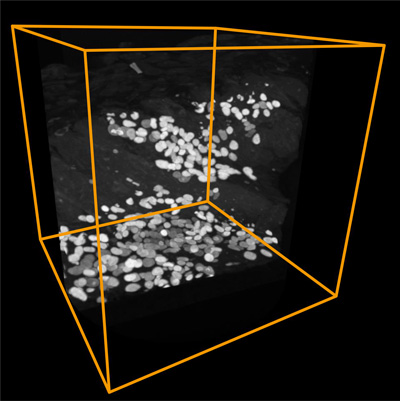

APEX2在來(lái)自健康人的人iPS細(xì)胞的細(xì)胞核中表達(dá),并誘導(dǎo)分化成心肌細(xì)胞。然后,將該iPS細(xì)胞衍生的心肌細(xì)胞移植到模型心肌梗塞模型小鼠中。移植后6個(gè)月,用X射線顯微鏡觀察顯示移植的心肌細(xì)胞的細(xì)胞核是白色的并且成功地可視化三維排列(圖1)。

圖1.心肌細(xì)胞移植后6個(gè)月的X射線顯微鏡圖像

(右)在3D重建圖像中,可以顯現(xiàn)移植的心肌細(xì)胞的三維排列。